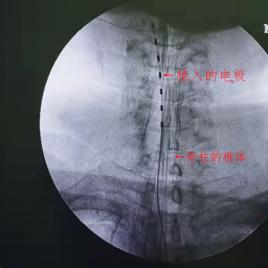

三、脊髓电刺激术SCS

治疗顽固性的神经病理性疼痛。

如图所示,通过将一根纤细的电极植入人体脊髓的背侧硬膜外腔,然后利用脉冲电流刺激脊髓神经以缓解疼痛。